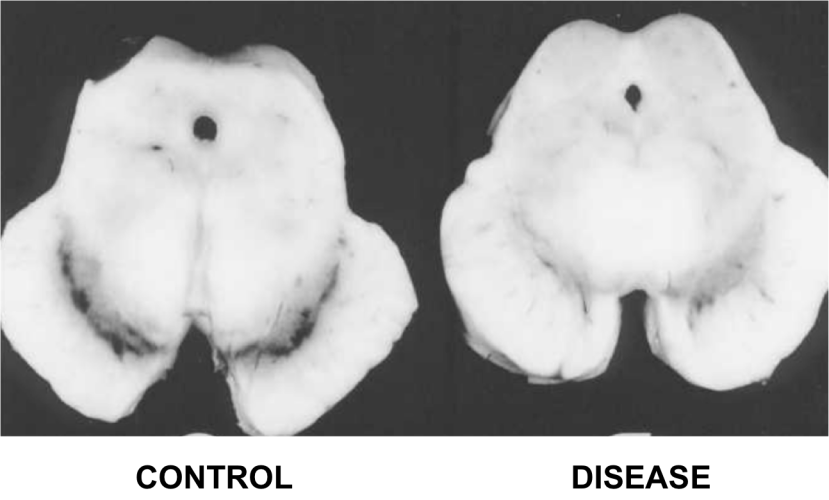

The dark pigmented dopamine neurons in the substantia nigra are reduced in the Parkinson’s disease brain (right). Source:Memorangapp

Earle examined 11 samples and compared them to unknown number of control samples and his results were a little startling:

The concentration of iron in Parkinsonian samples was two times higher than that of the control samples.